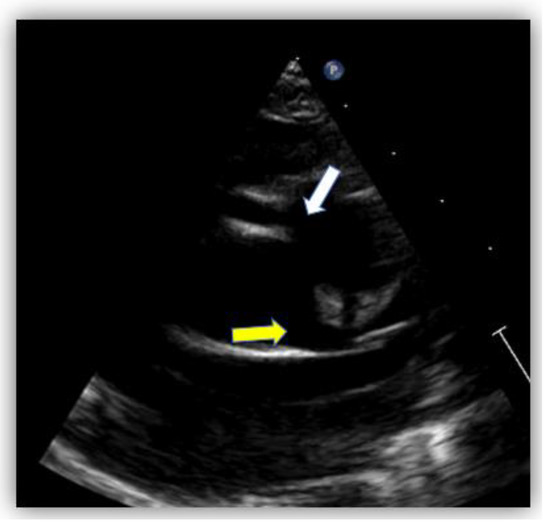

Challenging Diagnosis of Anomalous Origin of the Right Coronary Artery from the Pulmonary Artery

Anomalous origin of the right coronary artery (RCA) from the pulmonary artery, ARCAPA, is an extremely rare congenital heart disease. Only 200 cases were reported from 1885 to the present. Patients diagnosed with ARCAPA can be either asymptomatic or can experience symptoms, such as heart murmur, dyspnea, or angina, shortly after birth or around 40–60 years of life. Usually, those with isolated ARCAPA are diagnosed later in life compared to those who associate other structural cardiac defects. We report two cases of anomalous origin of the right coronary artery at the level of the pulmonary artery trunk (ARCAPA) that were diagnosed by invasive coronary angiography. Although asymptomatic, general recommendations suggest an early corrective intervention to prevent complications such as myocardial ischemia and cardiac dysfunction, which can lead to sudden cardiac death. Full article

Figure 1